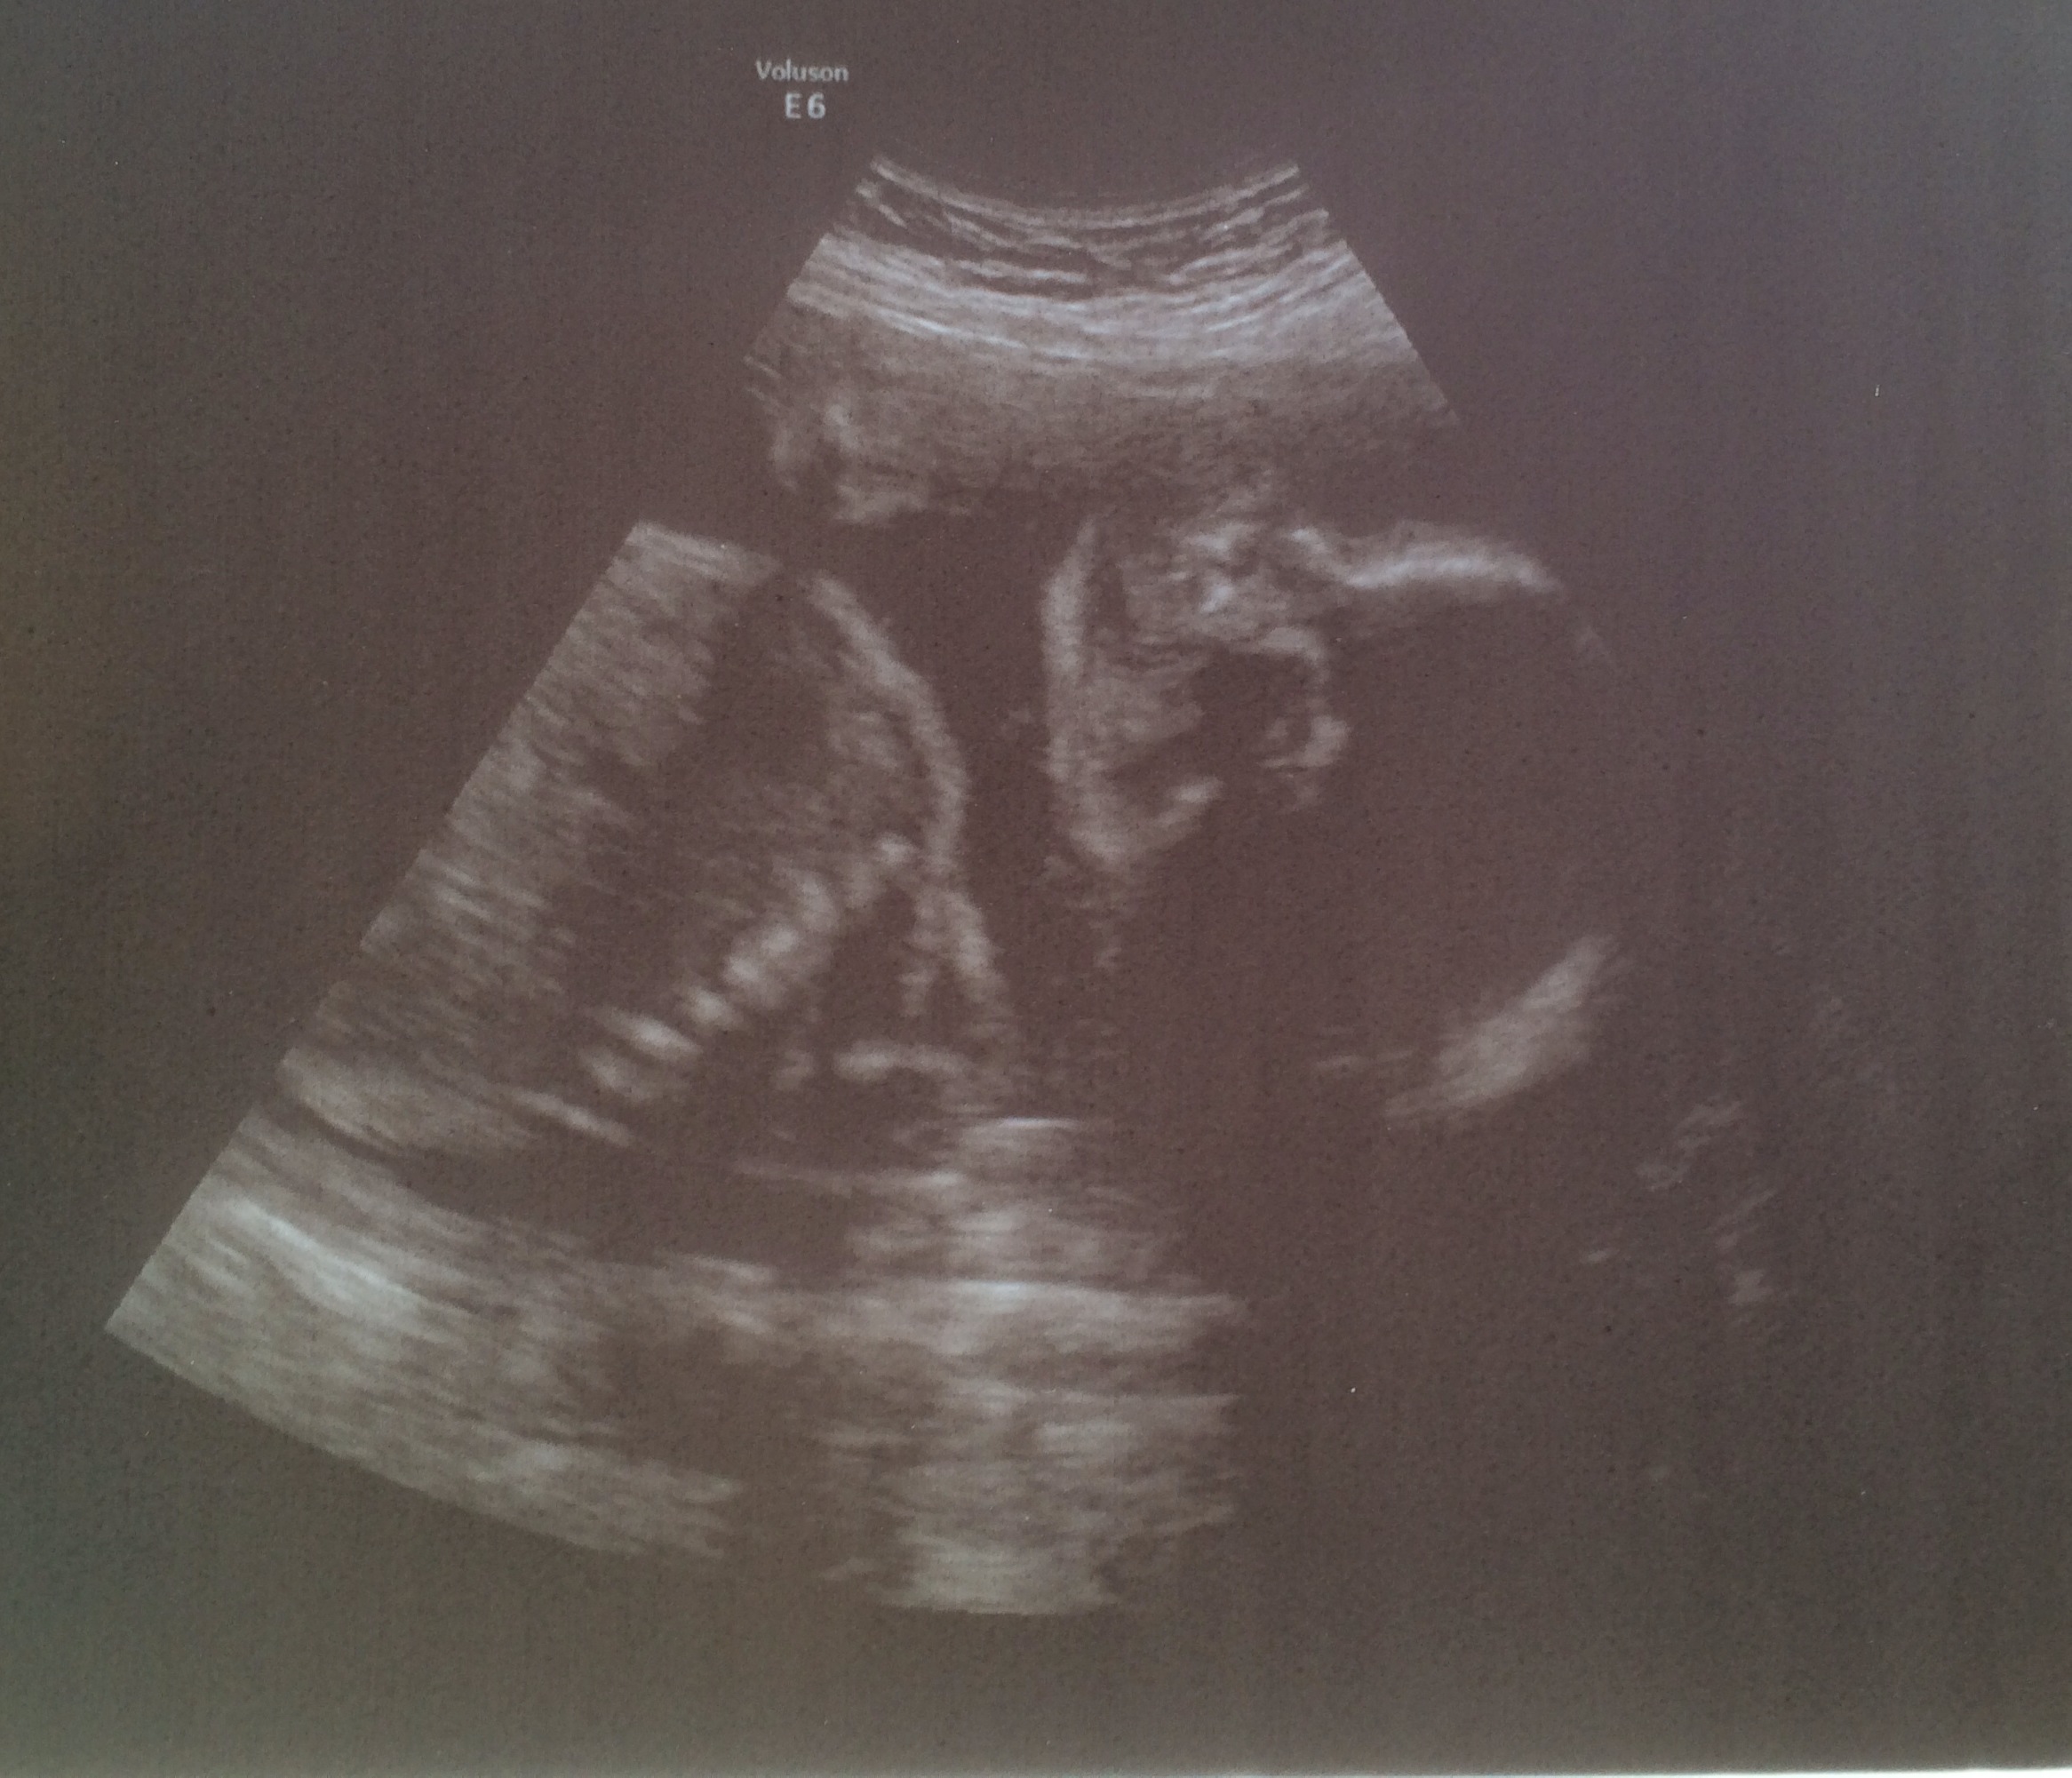

Diesmal gab es kein 3D-Bild ente lag nicht schön...aber das ist ja nicht schlimm...hab ein normales obwohl man da nicht viel drauf sieht...

Jetzt zu Ente...herzchen schlägt und er wiegt jetzt so 710g und ist so ca. 29cm groß...ein kleines propper Kerlchen.

Ente 24+2